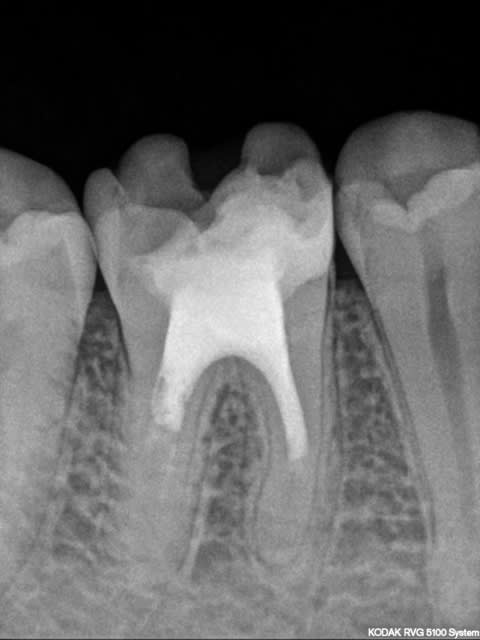

J'ai demandé au patient hier de récupérer son dossier chez ses 2 dentistes précédents . J'aimerais bien savoir à quel âge cette dent a été traitée.

La radio RVG de Newone'(merci pour elle!) nettement plus précise que la mienne confirme que la dent se porte plutôt bien , non ?